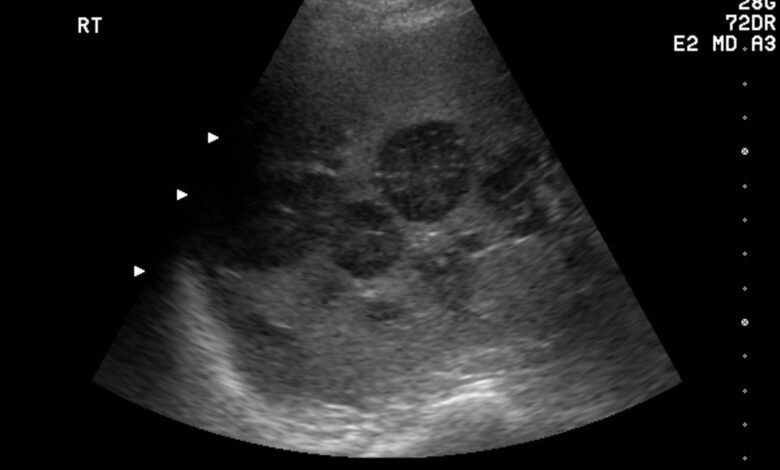

Ультразвуковое исследование (УЗИ) печени с допплерографией является важным методом диагностики заболеваний печени и желчного пузыря. При помощи УЗИ можно получить подробное изображение внутренних органов, определить их размеры, структуру и наличие патологий.

Допплерография — это дополнительный метод УЗИ, который позволяет оценить кровоток в сосудах печени. Этот аспект особенно важен при подозрении на цирроз, гепатит или опухоли печени.

Благодаря допплерографии специалист может выявить нарушения кровотока, определить скорость и направление движения крови в сосудах, что помогает в диагностике различных патологий.